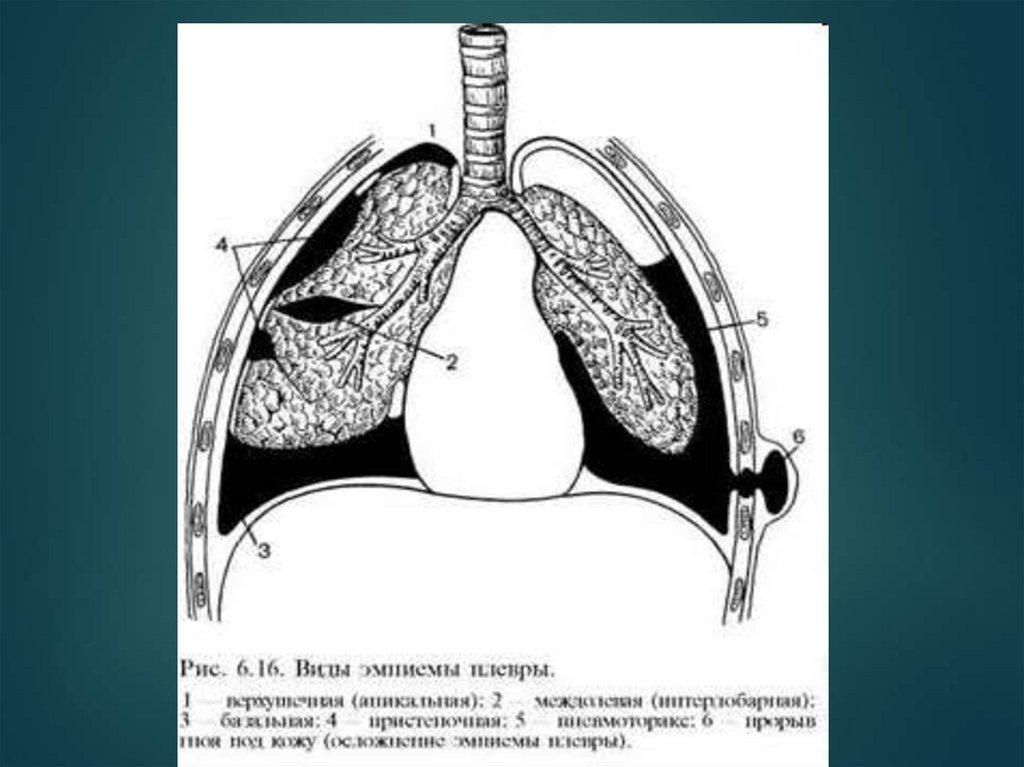

Эмпиема плевры

Клиника

Гнойное воспаление плевры, сопровождающееся

скоплением гноя в плевральной полости.

81. Клиника

Признаки интоксикации (лихорадка, тахикардия,

одышка, цианоз кожи и слизистых).

Отставание поражённой половины грудной клетки в

акте дыхания.

Перкуторное притупление лёгочного звука в проекции

гнойного очага.

Ослабление дыхания, голосового дрожания.

1 — участок плевральной

полости, заполненный

жидкостью

(притупленный или

тупой перкуторный

звук);

2 — линия Эллиса —

Дамуазо —

Соколова;

3 — треугольник

Гарленда

(тимпанический

перкуторный звук ателектаз);

4 — треугольник Грокко

— Раухфуса

(притупленный

перкуторный звук).